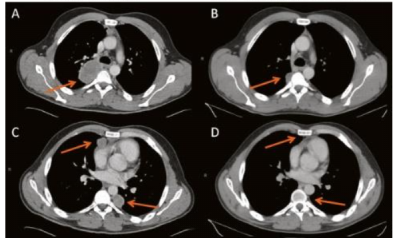

Kết quả sau điều trị bằng liệu pháp miễn dịch: Các khối u được thu nhỏ hoặc biến mất